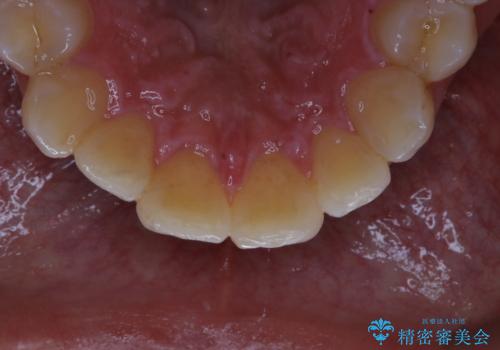

- 歯科でのクリーニングが5・6年ぶりで、全体をきれいにしたいとのことで来院されました。PMTC60分コースを行いました。

汚れを除去することにより、症状の早期発見につながります。

クリーニング希望の際には担当の歯科衛生士が、患者様1人1人の歯周病リスク・ブラッシングスキルなども確認します。

単なる磨き方の指導だけではなく、歯並びや歯肉の状態、ライフスタイルなどにより、患者様に適した歯ブラシや歯磨剤の選択をしたり、お口のお悩みについてのご相談も承っております。